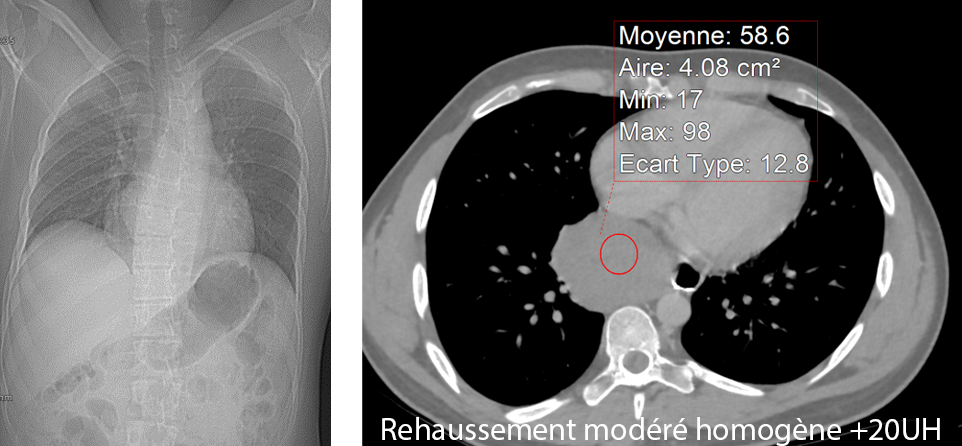

Patient de 35 ans, Pyrosis depuis plusieurs mois.

Pas d'amaigrissement

Patient non fumeur, non OH - non Tabac dépendant Examen clinique négatif. Pas d’ADP de Virchow Troisier.

QUEL EST VOTRE DIAGNOSTIC ?

A – Kyste bronchogénique

B – Œsophagite à éosinophiles de l’adulte

C – Léiomyome

D – Lymphome

E – Mélanome malin de l’oesophage